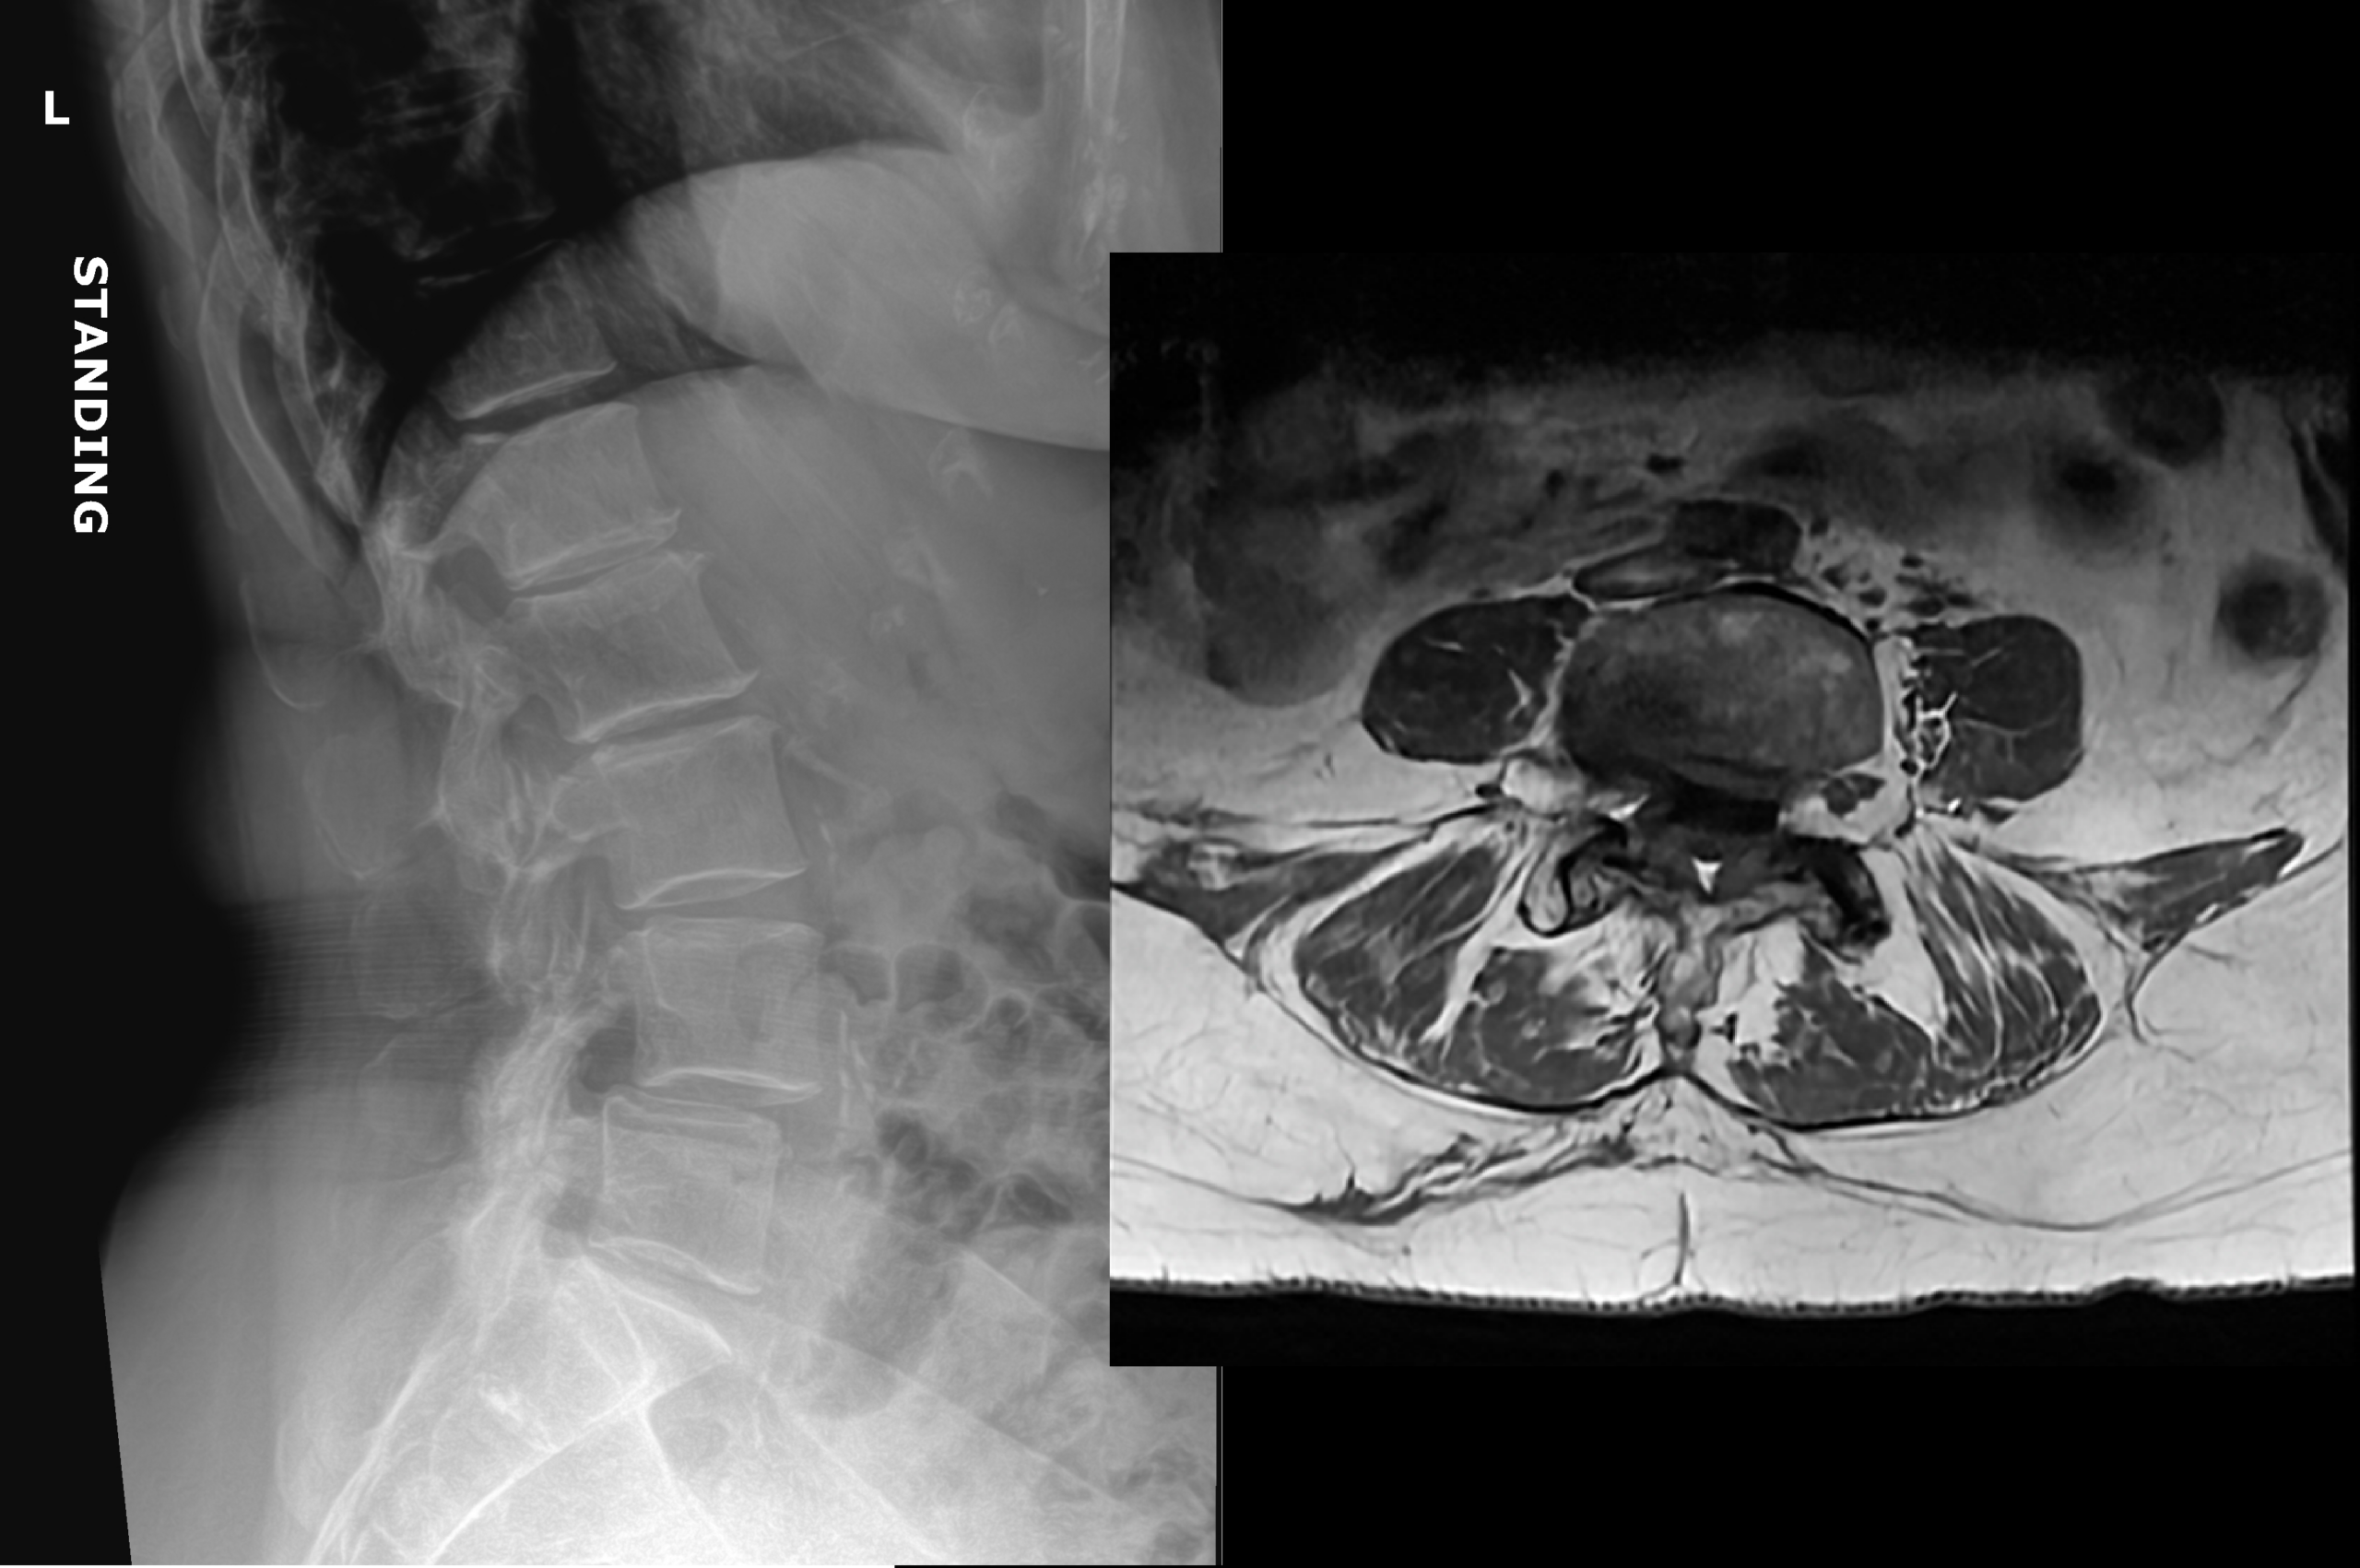

An 80 year old female presents to your office with a left ring finger deformity after a fall one week ago. She initially went to urgent care and xrays were unremarkable for a fracture (Figures 1 and 2). A photo of her left ring finger is shown in figure 3. On physical exam the left ring finger is in hyperextension at the PIP joint and flexion at the DIP joint. She able to flex her PIP joint with full motion. What is the best treatment option?